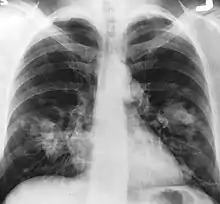

An X-ray scan indicating abnormal masses in the lungs.